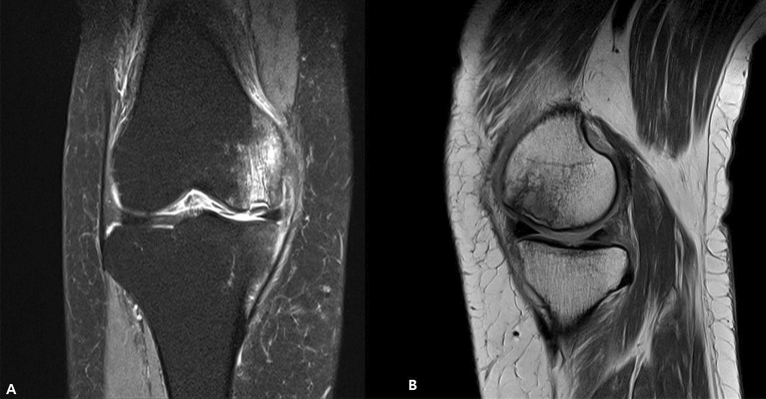

All patients received preoperative MRI scans. MRI characteristics of SIKF include a subchondral area of low signal intensity on T2-weighted images, focal epiphyseal contour depressions, and lines of low signal intensity in the affected condyle19. For the present study, a SIFK lesion was defined as a low signal intensity focus beneath the articular surface in the weight-bearing area of the tibiofemoral compartment on T1-weighted images and a central focal linear subchondral low signal intensity or focal subchondral bone plate impaction with marked surrounding bone marrow edema on fat-suppressed T2-weighted images20 (Fig. 2). The lesion size was measured on coronal and sagittal MR images, and the largest lesion was measured in length (sagittal), width (coronal), depth (deepest portion measured in either coronal or sagittal view)21 (Fig. 3).

Figure 2.

Coronal T2-weighted MRI of SIFK (left). Sagittal T1-weighted MRI (right). MRI, magnetic resonance image. SIFK, subchondral insufficiency fracture of the knee.